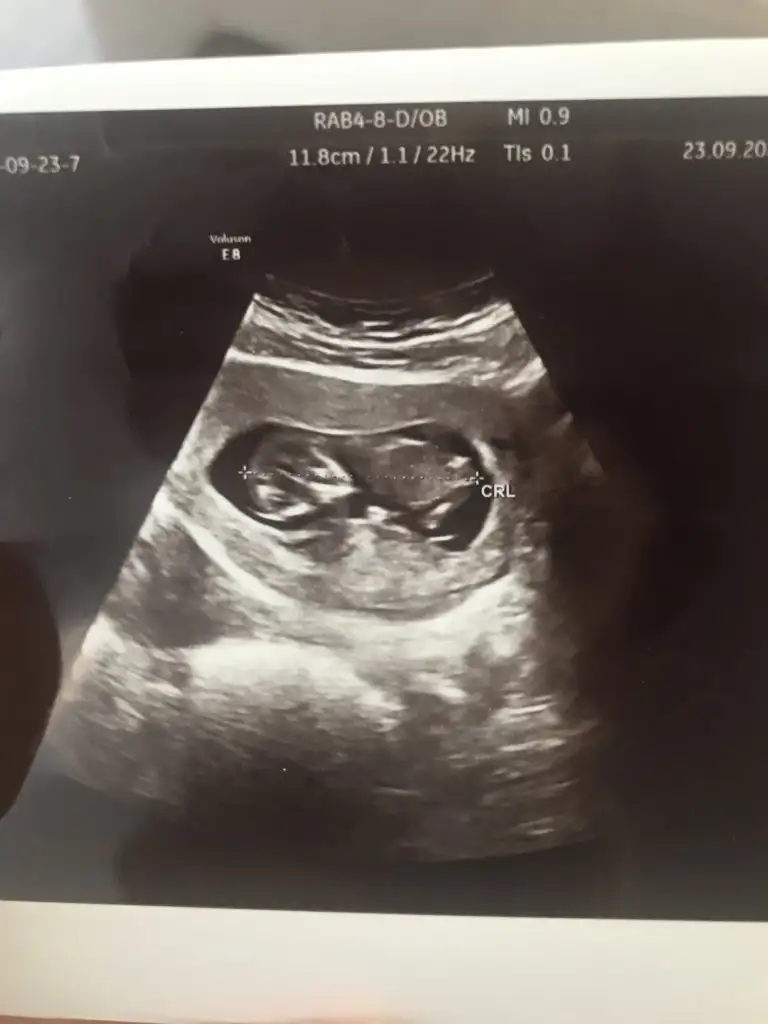

yarın benimde kontrolüm var geçen hafta rahatsızlandıgımda görmeme rağmen bende çok özledim merak ediyorum yaa hayırlısıyla sağlıkla ilerlesin inşaallah hamileliklerimiz

benim ilk zamanki şişkinliğim indi birde zayıfladım biraz kusmaktan olsa gerek cok takılmıyorum onlar iyi olsunda zaten kilo illa alıcaz hele ikiz kilosu daha bi gözümü korkutmuyo değil